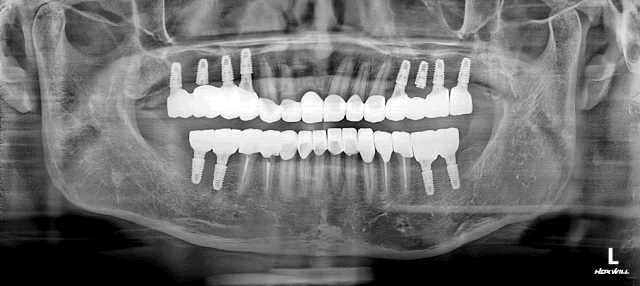

우수한 임플란트 병원은 반드시 철저한 초진 검사를 실시합니다. 구강 내 검사뿐 아니라 파노라마 X선이나 CT 촬영을 통해 뼈의 상태와 신경 위치 등을 정확히 파악해야 합니다.

임플란트는 의료진의 경험이 직접적으로 결과에 영향을 미치는 시술입니다. 따라서 연간 수행하는 임플란트 사례 수와 구체적인 사례 사진을 확인하는 것이 좋습니다.